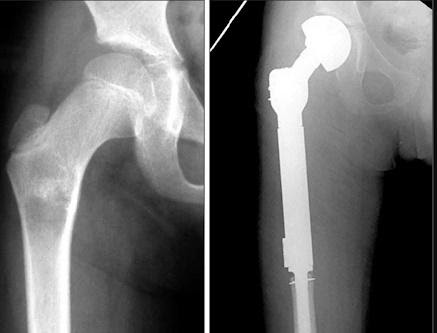

Be vigilant for childhood conditions such as Perthes diseases in 5-10 year olds (see figure 14 [3]) and Slipped Upper Femoral Epiphyses in 10-15 year olds (see figure 15).

Missing these can condemn the child to accelerated loss of function, osteoarthritis, and early hip replacement in adulthood. They need orthopaedic input. Again, have a low threshold for imaging.